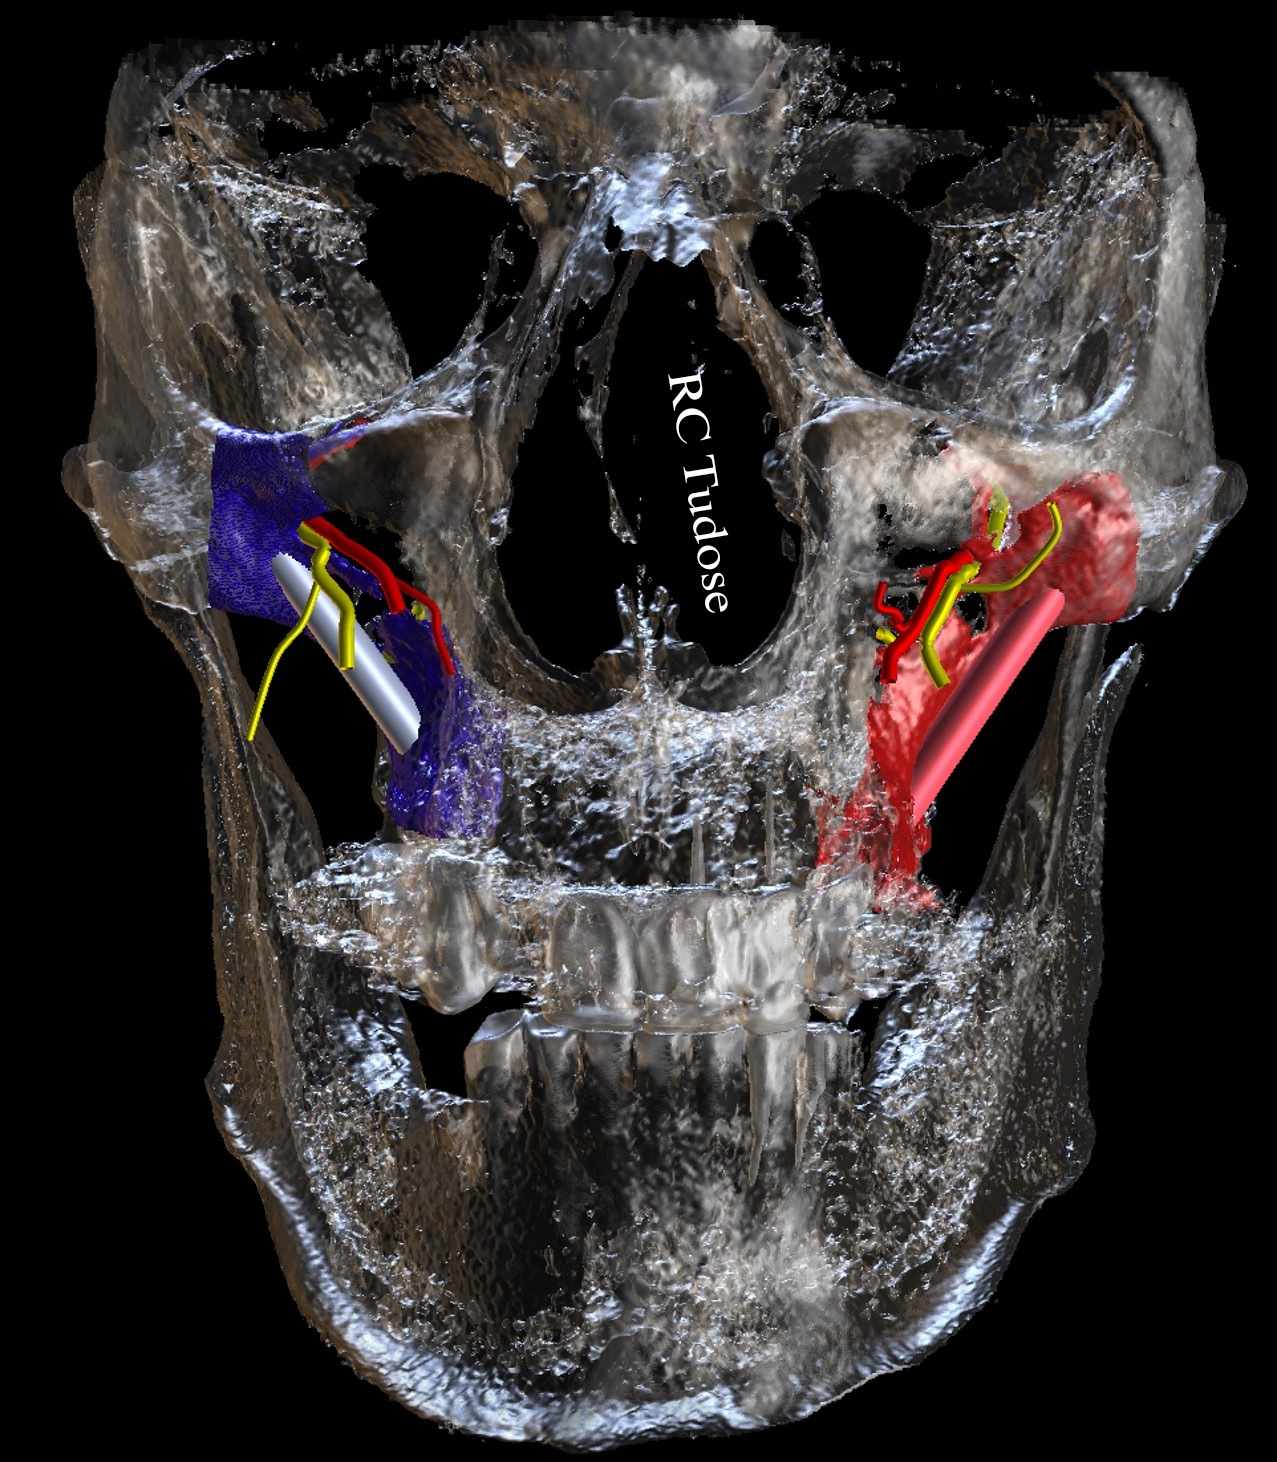

Oral Presentation - CBCT assessment of the greater palatine canal

Oral Presentation - The Zygomatic Implant: An anatomical view of the potential risks